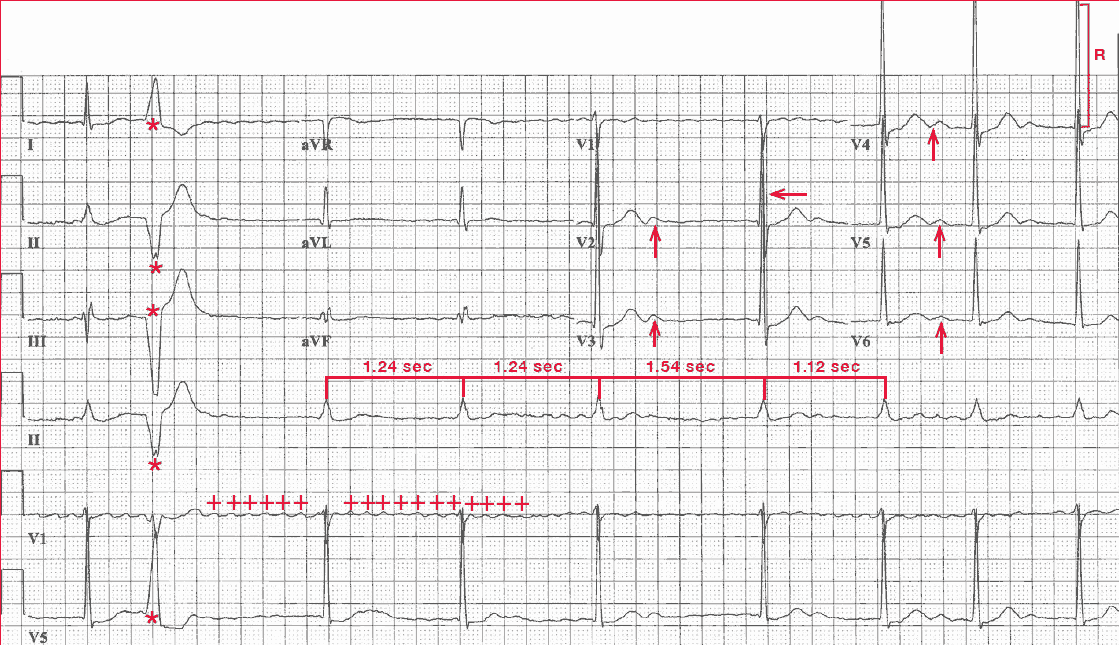

The rhythm is irregularly irregular at a rate of 54 bpm. There are no obvious organized P waves; rather, there are fine and rapid waveforms (+) that are irregular in amplitude, morphology, and interval. These are atrial fibrillatory waves and the underlying rhythm is atrial fibrillation with a slow ventricular response.

A single premature ventricular complex can be seen (second QRS complex [*]). The QRS complex axis, duration (0.10 sec), and morphology are normal. However, there is early transition (ie, a tall R wave in lead V2 [←]) as a result of counterclockwise rotation in the horizontal plane.

The amplitude of the QRS complex is tall (R-wave amplitude in leads V3-V4 = 33 mm [ ] ]), which is diagnostic for left ventricular hypertrophy (ie, S-wave or R-wave in any precordial lead ≥25 mm). The QT/QTc intervals are normal (460/440 msec).

In addition, prominent U waves are seen in leads V2-V6 (↑). It is often seen as a low-amplitude, positive waveform in the right precordial leads (V1-V3) and it often becomes more prominent with bradycardia.

However, an increase in the amplitude of the U wave or its presence in the lateral precordial leads (V4-V6) is suggestive of hypokalemia, which is likely the result of the addition of hydrochlorothiazide. This is a thiazide diuretic, and one of the most common side effects of this class of drugs is hypokalemia.